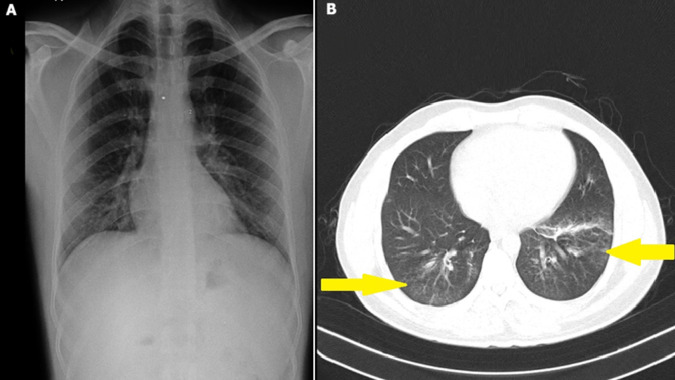

Pulmonary toxoplasmosis in the immunocompetent.